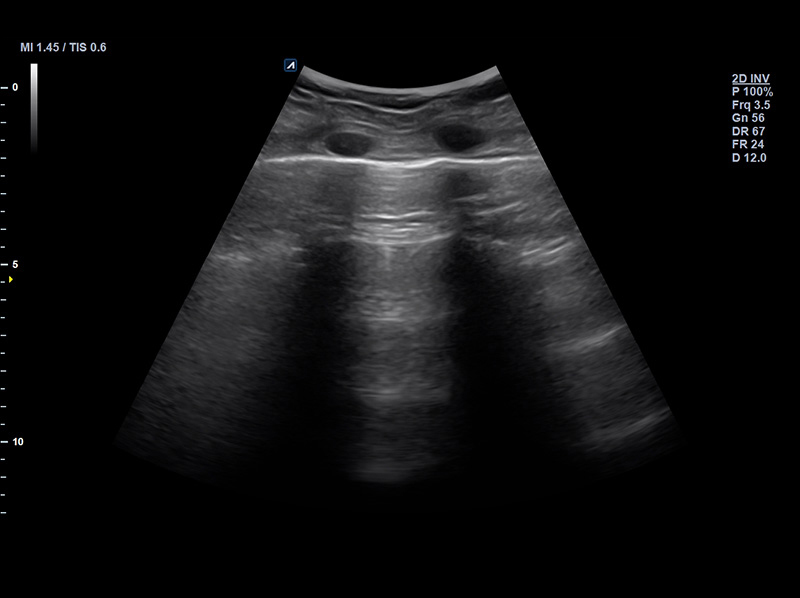

SC1-7H

X+ Crystal Signature™ convex transducer(1~7MHz)

Application:

Abdomen, EM, Gynecology, Obstetrics, Pediatric, Urology